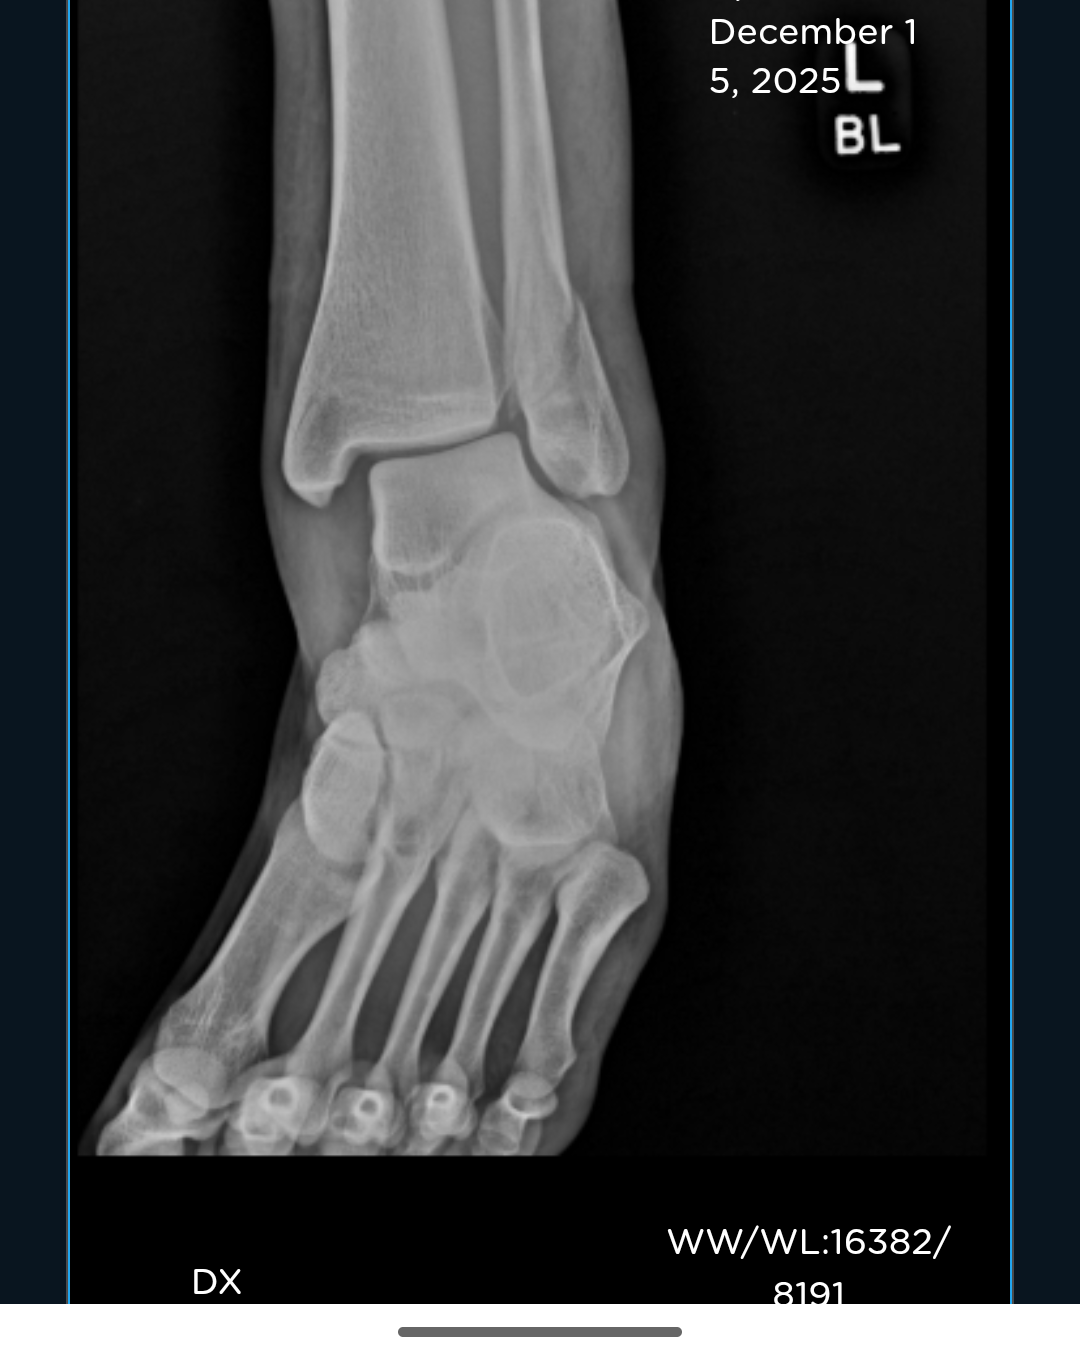

Due to the nature of my injury, a spiral fracture in my fibula and a displaced tibia, I now need surgery on it immediately. Without insurance, my out of pocket cost will be $10-13k on top of what I've already had to pay out of pocket just to get looked at and told to go elsewhere. At this time, I am unable to pay the amount required for the surgery. As I'm uninsured, currently not working and won't be able to for quite some time while I'm recovering, I'm hoping to see if I can somehow manage to come up with the money and so here I am.